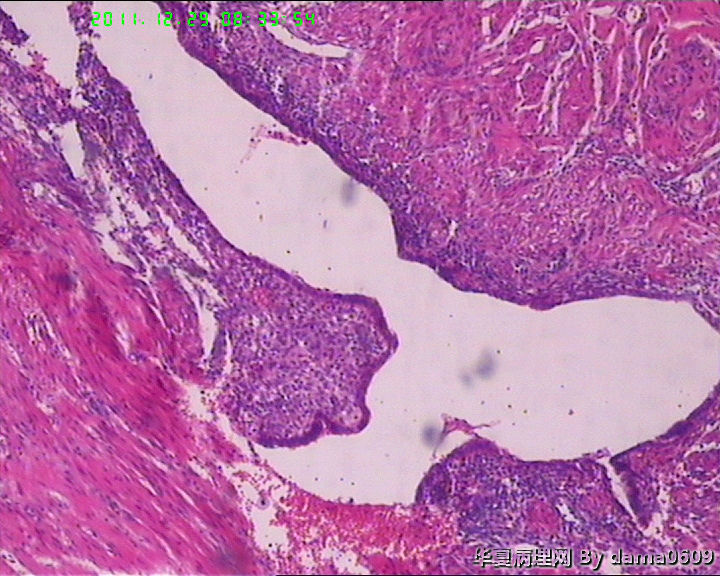

另一为小块囊壁样组织。镜下见卵巢间质内大量淋巴细胞、嗜酸性粒细胞浸润,间质出血。囊壁囊腔一侧见组织细胞、嗜中性粒细胞浸润,小血管增生(图1-9)。局灶见较多的平滑肌组织,内见有异位的子宫内膜组织(图10、11、12)。另于平滑肌组织间见到散在的小腺体(图13~30)。学生不解:1、老年人卵巢内可以出现平滑肌组织,如卵巢门处。此例如此多的平滑肌是正常的吗? 2、平滑肌间的小腺体若是异位的子宫内膜腺体但周围不见内膜间质成分。若非内膜异位腺体,学生又不知如何解释,尤其图19、20、21。请老师们指点迷津。感谢!!